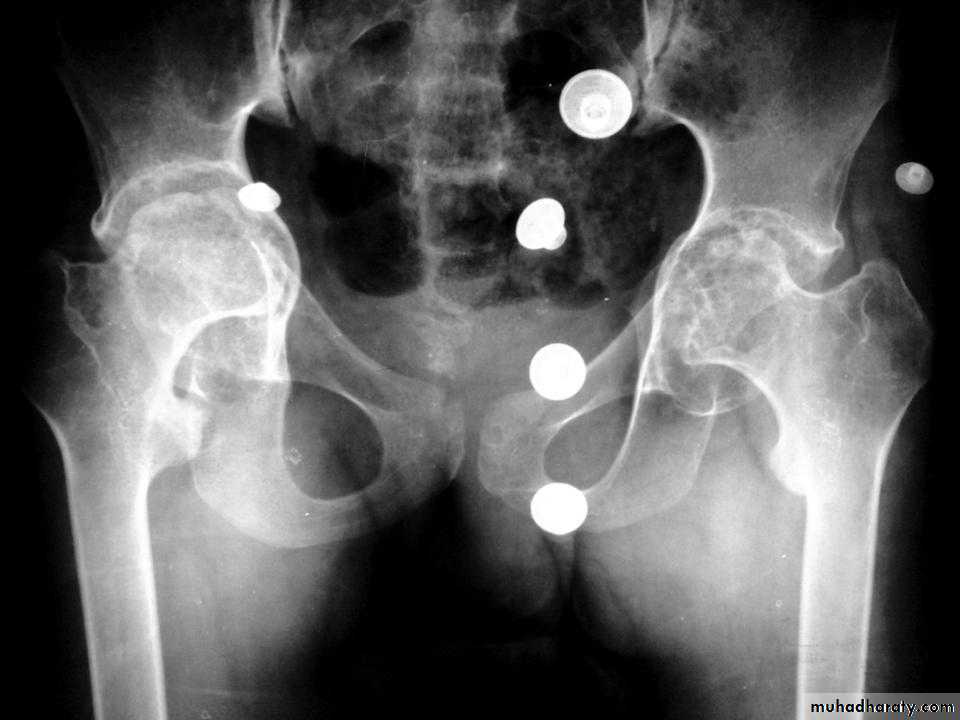

• * Arthritis of proximal joints (hip > shoulder) in 50% ,erosions and osteophytes

DEVELOPMENTAL DYSFLASIA OF HIP (CONGENITAL DISLOCATION OF THE HIP)

• An abnormally lax joint capsule allows the femoral head to fall out of the acetabulum, leading to deformation.• Predisposing factors for the development of CDH are:

• * Abnormal ligamentous laxity (effect of estrogen; fema1e:male = 6:l)

• * Acetabular dysplasia .

• CDH occurs most commonly (70%) in the left hip. Bilateral involvement is seen in 5%.

• Radiographic features

• US (commonly used today) at 1-3 months

• * Normal femoral head is covered at least 50% by acetabulum , In CDH < 50% of femoral head is covered by acetabulum .

Plain film

At 3-6 months :By doing special veiw (Von Rosen veiw )by abduction of the thigh 45 degree and internal rotation .

In DDH the lines that drown through the femura will meet in higher level than the normally should at lumbosacral joint .

6 months and later

* AP veiw ( femural epiphysis are visualized ):* Superolateral displacement of proximal femur (disturbed shenton’s line )

* Increase in acetabular angle

* Small capital femoral epiphysis

Femoral head is located lateral to Perkin's line

* Other features that are sometimes present

Abnormal sclerosis of the acetabulum

Shallow acetabulum

Formation of a false acetabulurn

Delayed ossification of femoral head